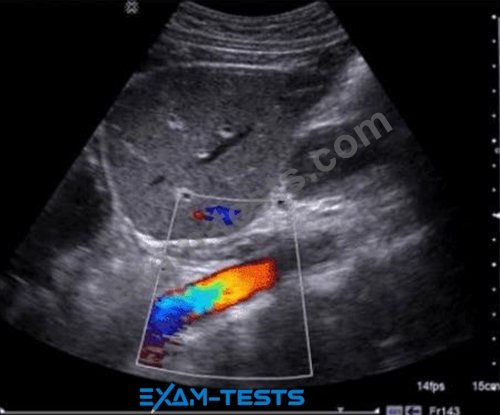

Question 100

What adjustment is needed to optimize the color in the image below?